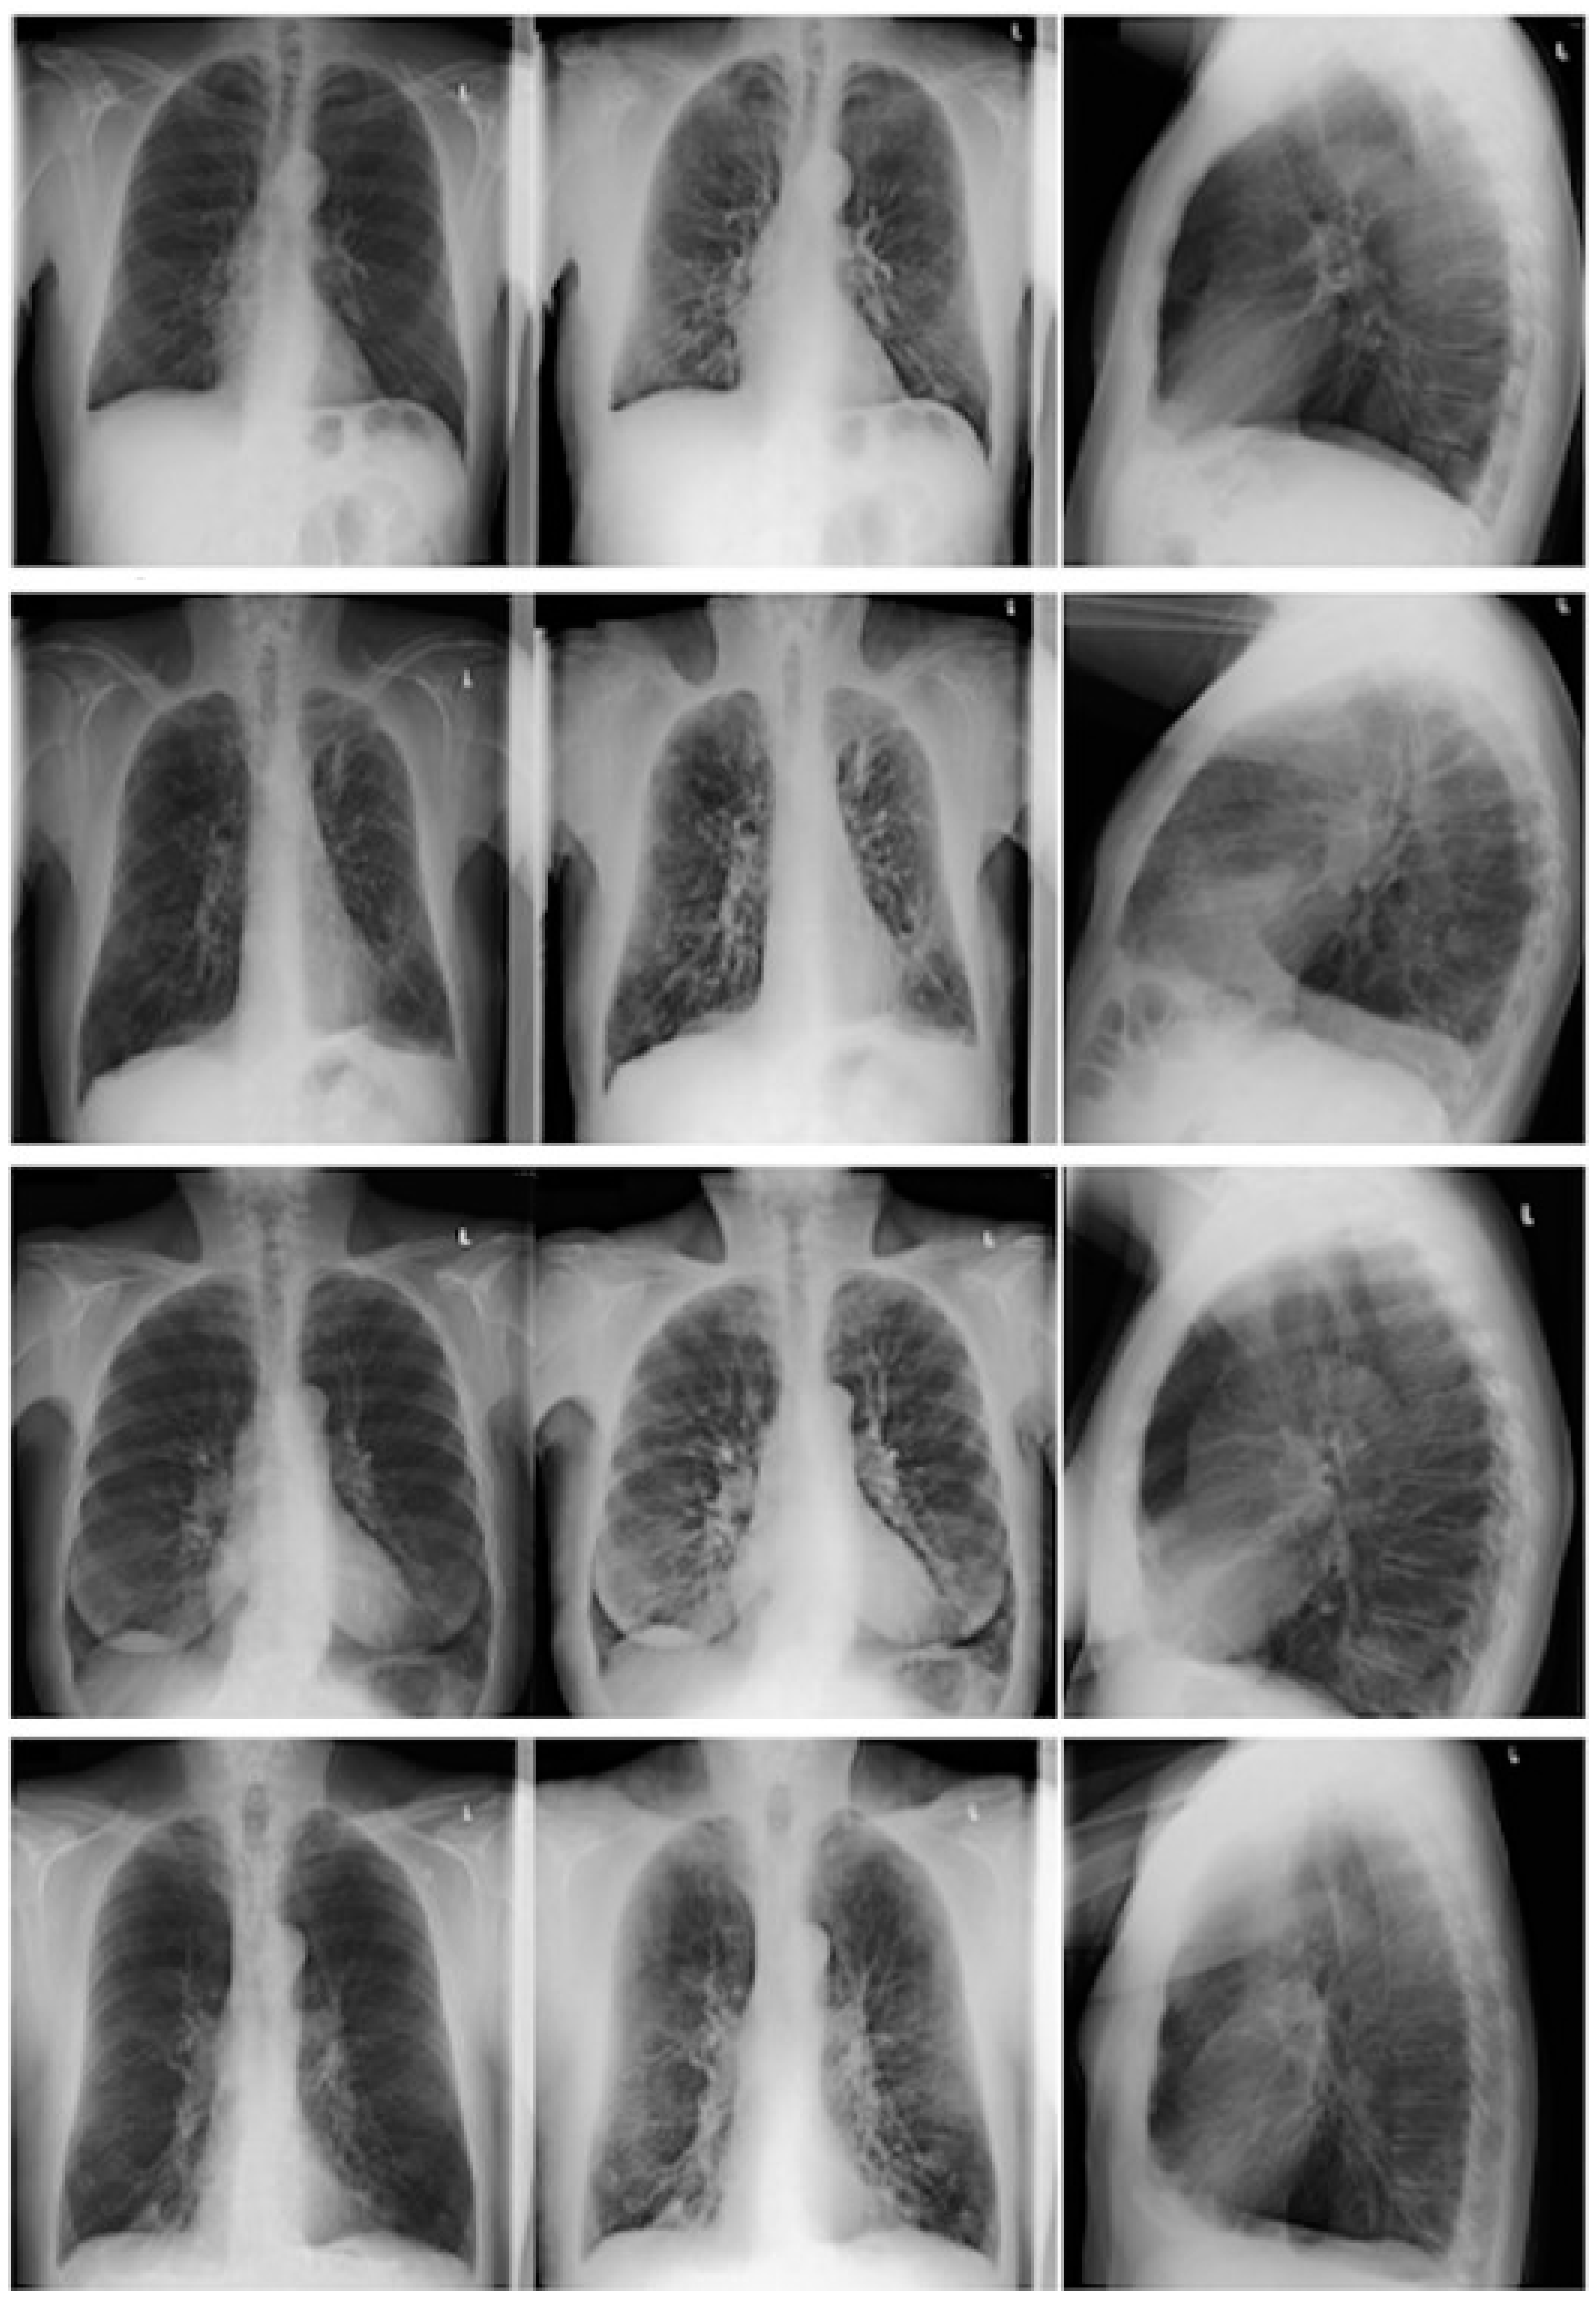

2.3.1. CR/DE Image Analysis

3.5. CR and DE Image Analysis